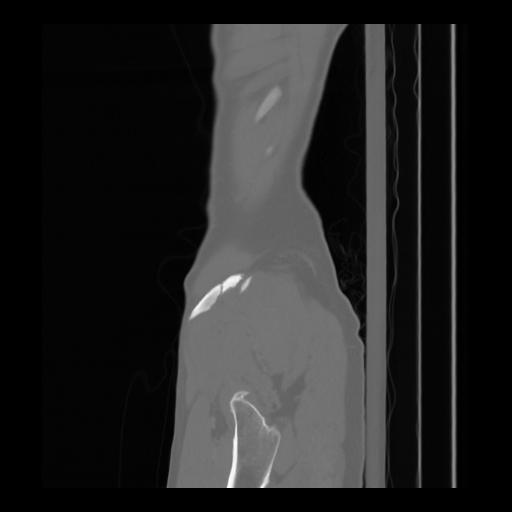

36 CUERPO,CE,Sagittal,3.000,CUERPO,Sagittal,